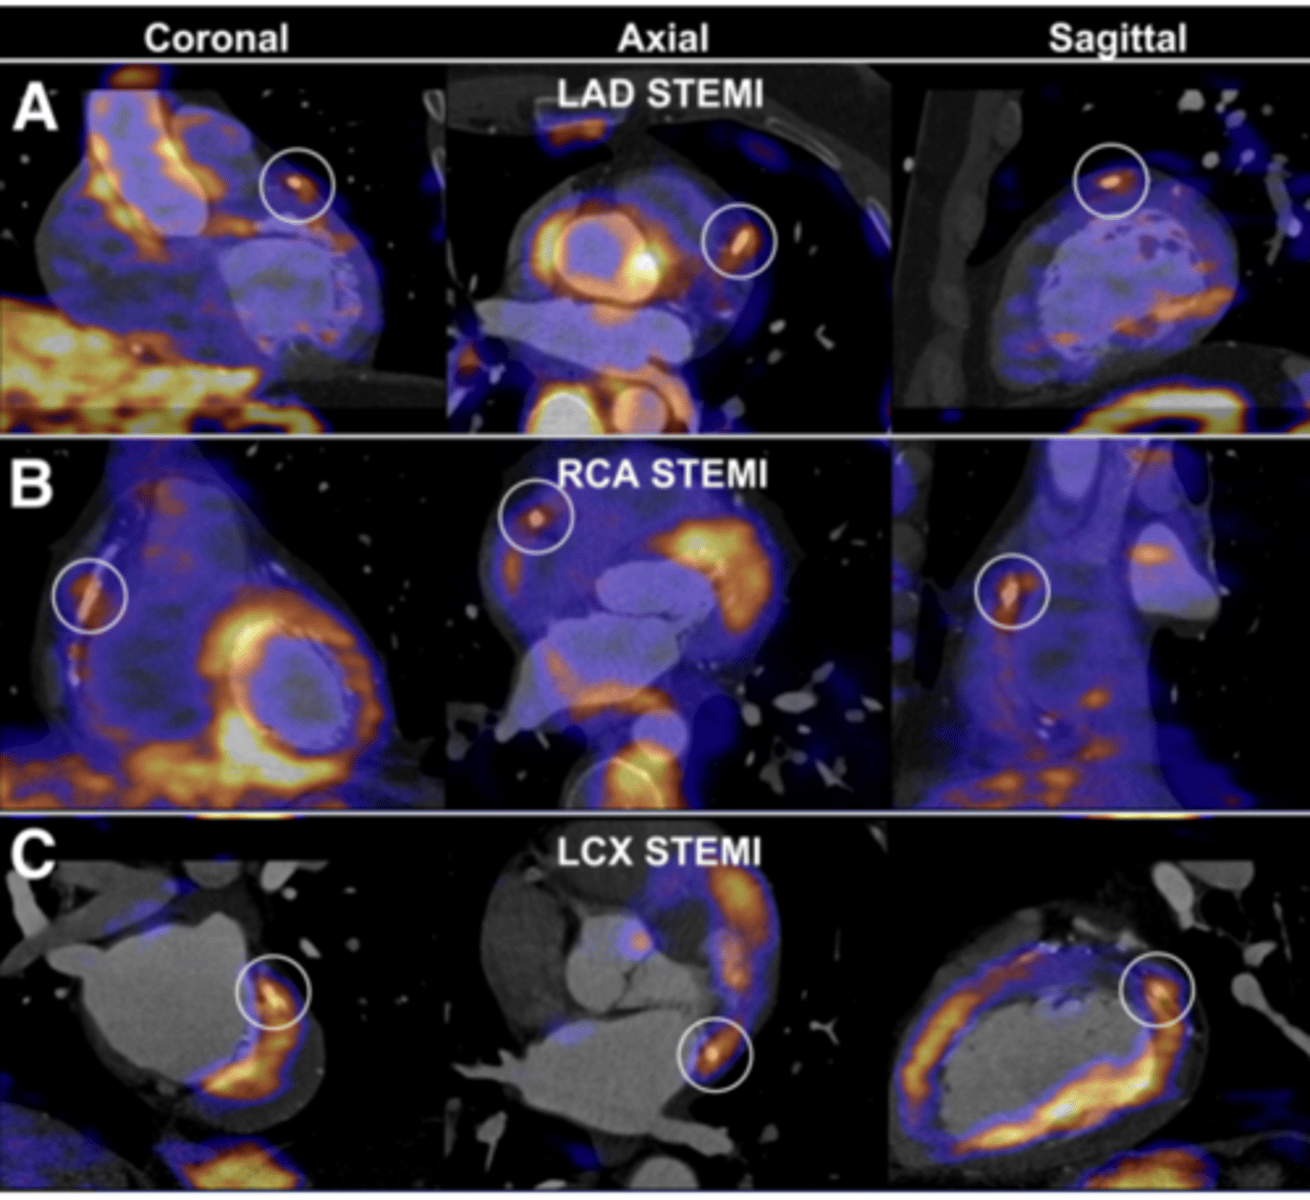

PET scan

Measures important body functions, like blood flow, O2 use, & glucose metabolism

-Used to evaluate tumors & cancers, myocardial function, & brain function

<p>Measures important body functions, like blood flow, O2 use, &amp; glucose metabolism</p><p>-Used to evaluate tumors &amp; cancers, myocardial function, &amp; brain function</p>

True/false: A PET scan can be used alone or in conjunction with a CT scan.

True